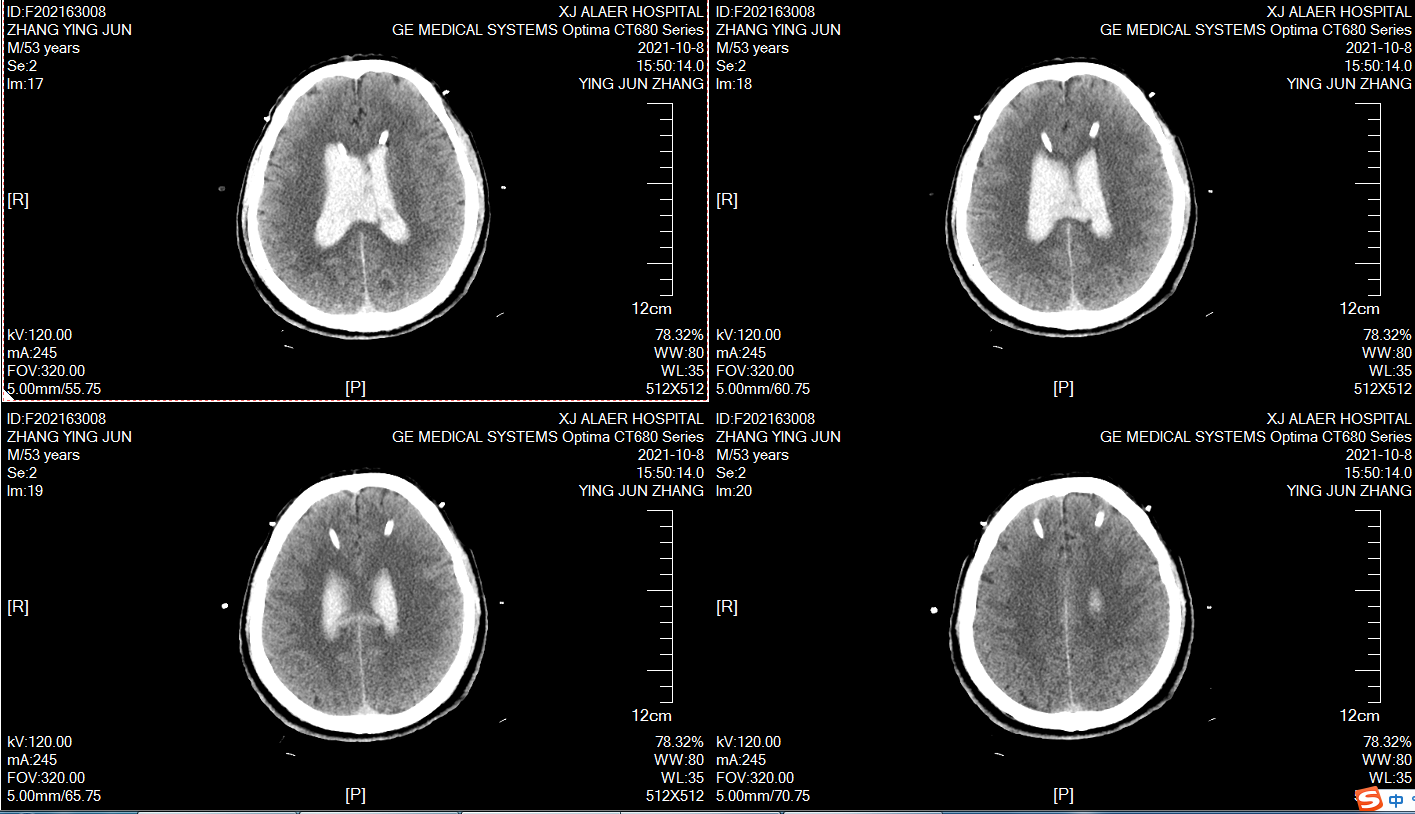

术前颅脑CT,男性,59岁,突发意识不清2小时,目前昏迷,GCS6分,右侧瞳孔4mm,左侧瞳孔2mm,脑室出血,烟雾病!